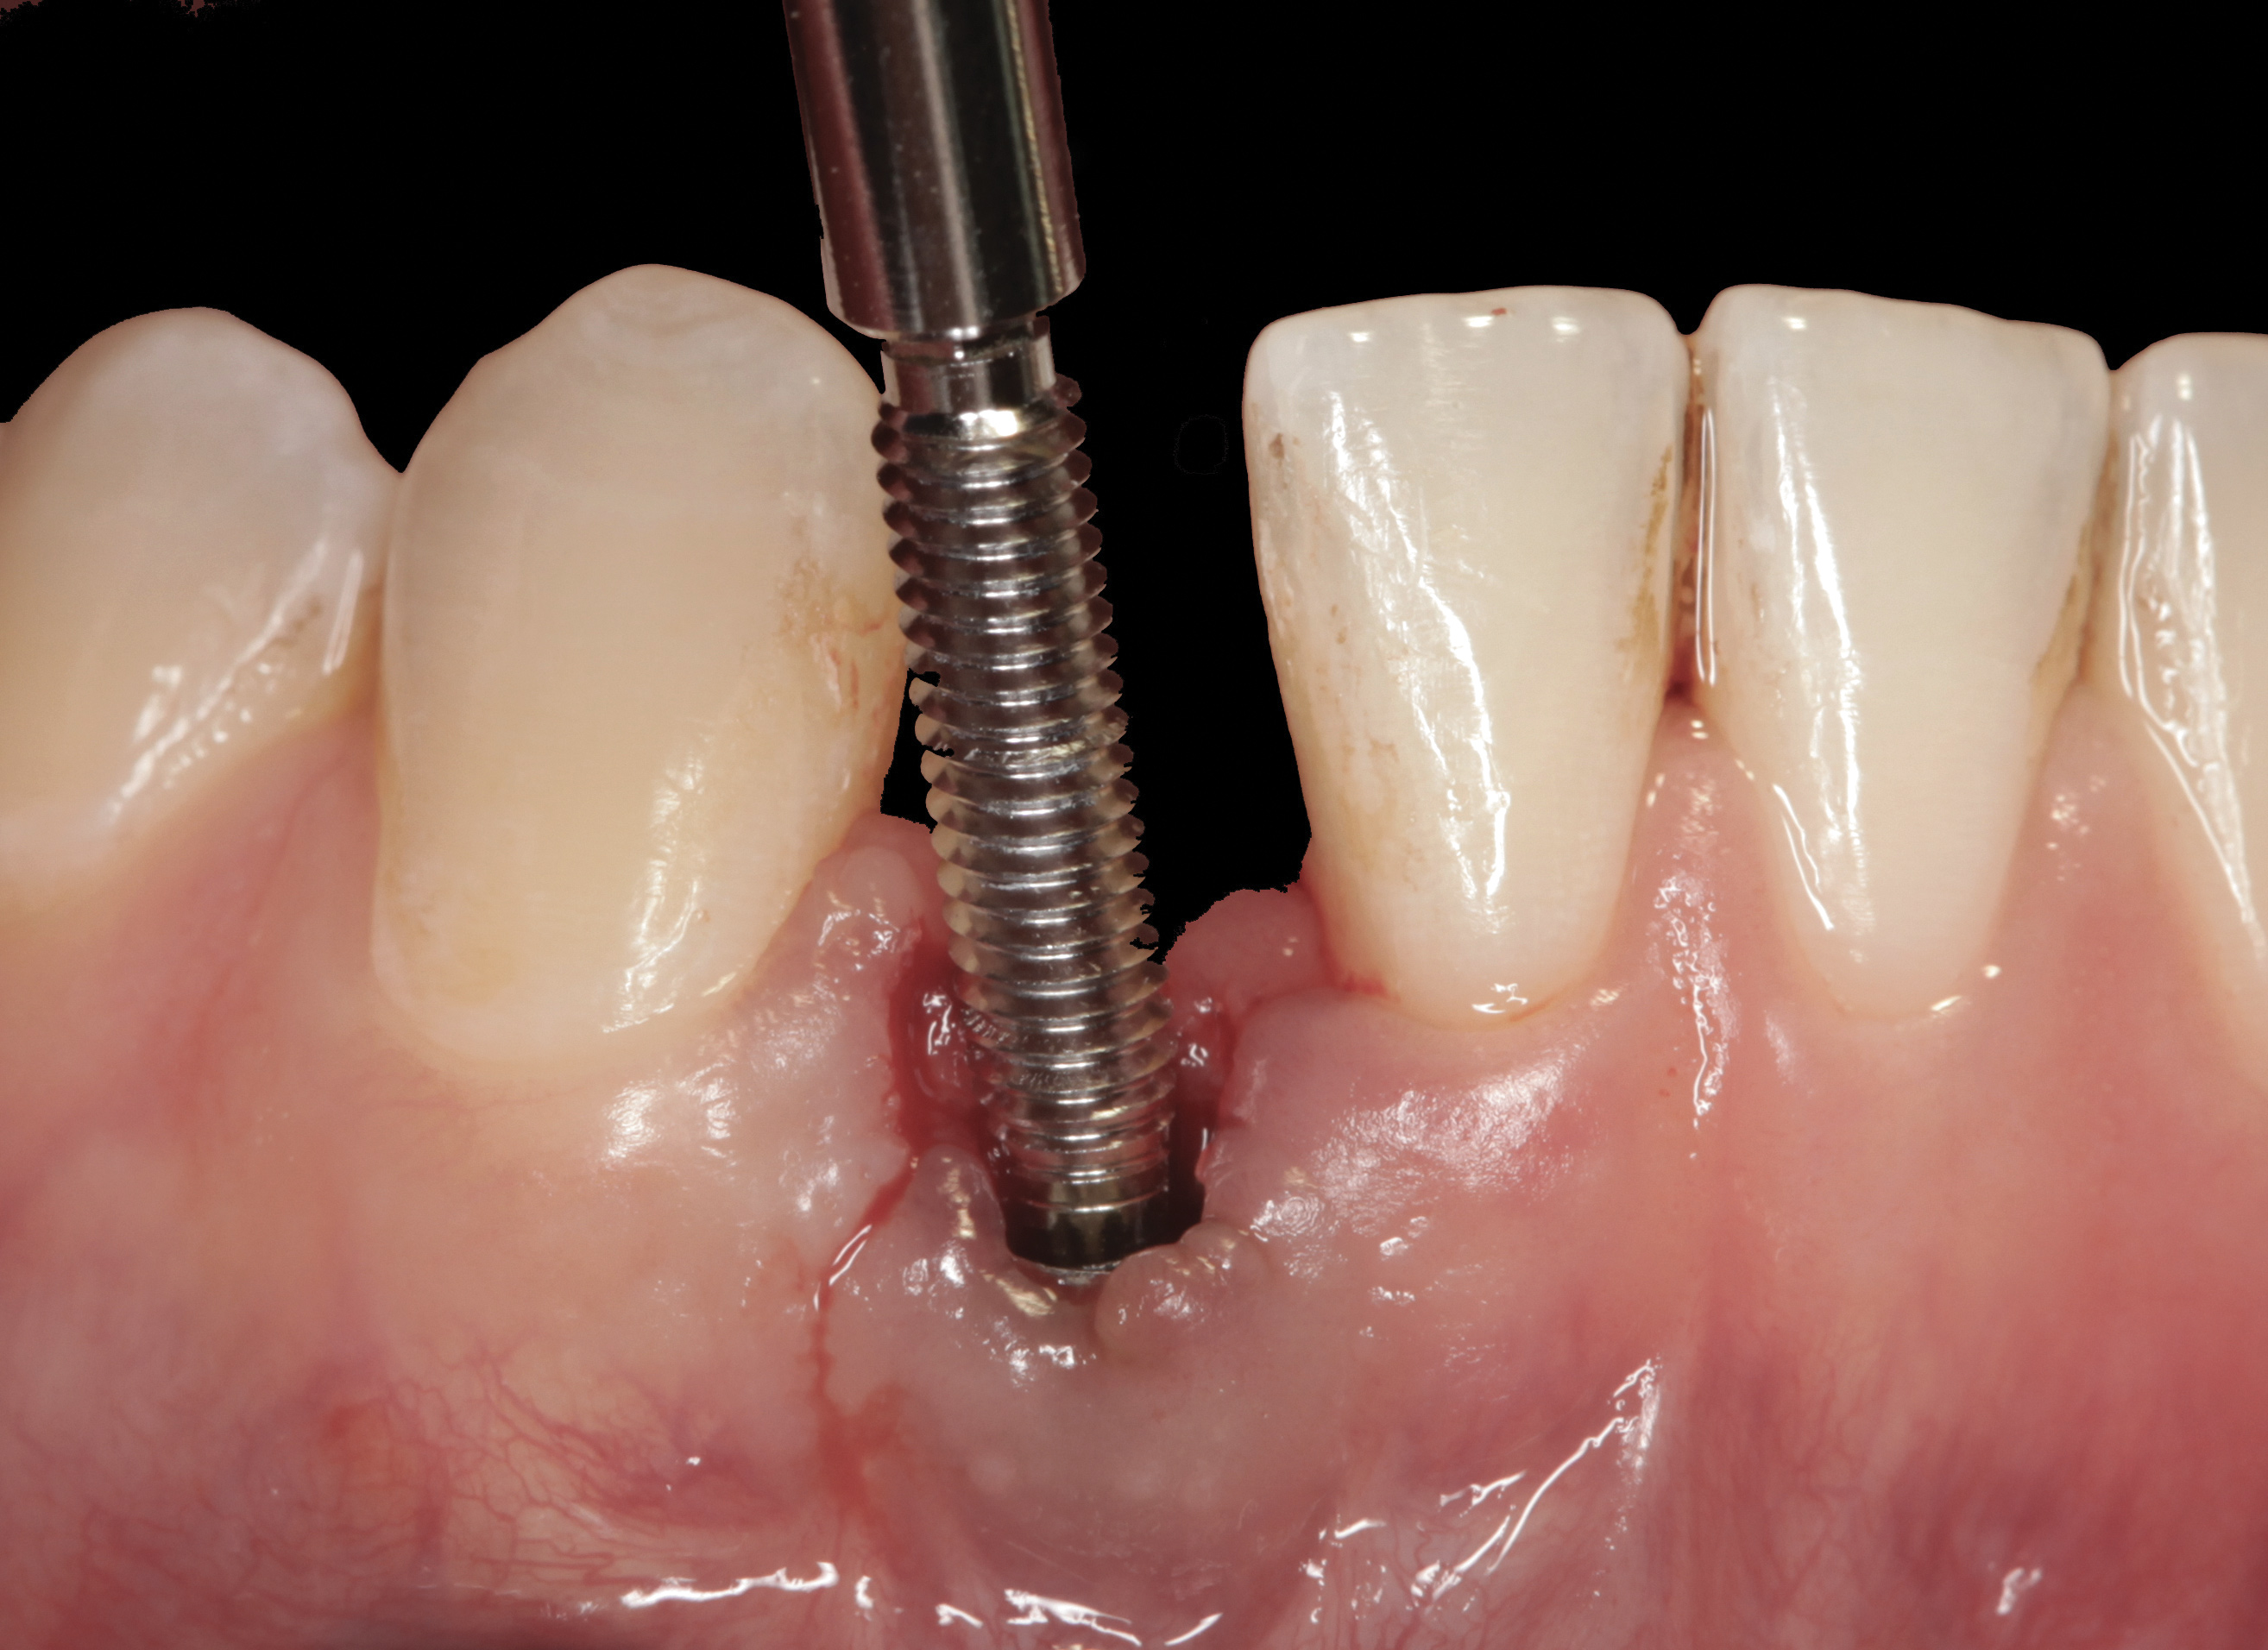

Fig 37. The reverse-torque driver can put up to 450 Ncm of force to disrupt osseointegration.

Figure 37

Fig 38. A reverse-torque screw was placed into the implant.

Figure 38

Fig 39. A counter-torque device was placed over the reverse-torque screw.

Figure 39

Fig 40. The implant was easily unscrewed within minutes in a minimally invasive manner with less trauma to the surgical site.

Figure 40

The crown and screw-retained custom abutment were removed, and a surgical cover screw was placed into the implant, thereby allowing spontaneous gingival augmentation in situ (Figure 33 and Figure 34). Note that the lingual aspect of the implant site was significantly more coronal than the labial aspect, which was positive because the defect would be limited to a facial–lingual defect. A fixed RBR bridge was cemented on the adjacent teeth and used as a tooth-supported transitional provisional restoration (Figure 35). A few weeks were allotted to let the soft tissue heal and migrate around the cover screw (Figure 36) to see if there would be complete coverage, thereby allowing a soft-tissue augmentation procedure to be performed with primary flap closure as in clinical scenario No. 2. The major obstacle in achieving a positive tissue response was that the implant depth was also deficient because the implant–abutment connection was at the level of the free gingival margin. It was decided that the best treatment option would be to remove the implant. A high-powered reverse-torque device (Fixture Remover Kit, NeoBiotech, www.neobiotechus.com) was used to remove the implant atraumatically (Figure 38 through Figure 41). The implant socket was allowed to heal for several months not unlike an extracted tooth (Figure 42). A new implant was placed in a better position from both a restorative and esthetic perspective (Figure 43), and after a few months of healing, a new crown was made (Figure 44). A satisfactory functional and esthetic result was achieved (Figure 45 and Figure 46) without employing pink porcelain.